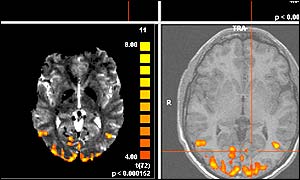

Brain scans showing activity when people see (copyright University of Leicester)

Brain scans showing activity when people see

Scientists are hoping to discover more about eye diseases by "lighting up the brain".

The team from the University of Leicester hope that using a special scanning technique will allow them to see exactly what happens in the brains of patients suffering from such diseases.

But the Leicester team are using a technique called functional MRI (fMRI), rarely used to study eye diseases, to examine what happens in the brain when we see, and when there are problems with sight.

fMRI allows researchers to see changes in blood flow in the brain that accompany brain activity.

This means scientists can see which parts of the brain become active, or "light up", as people look at different pictures and patterns.